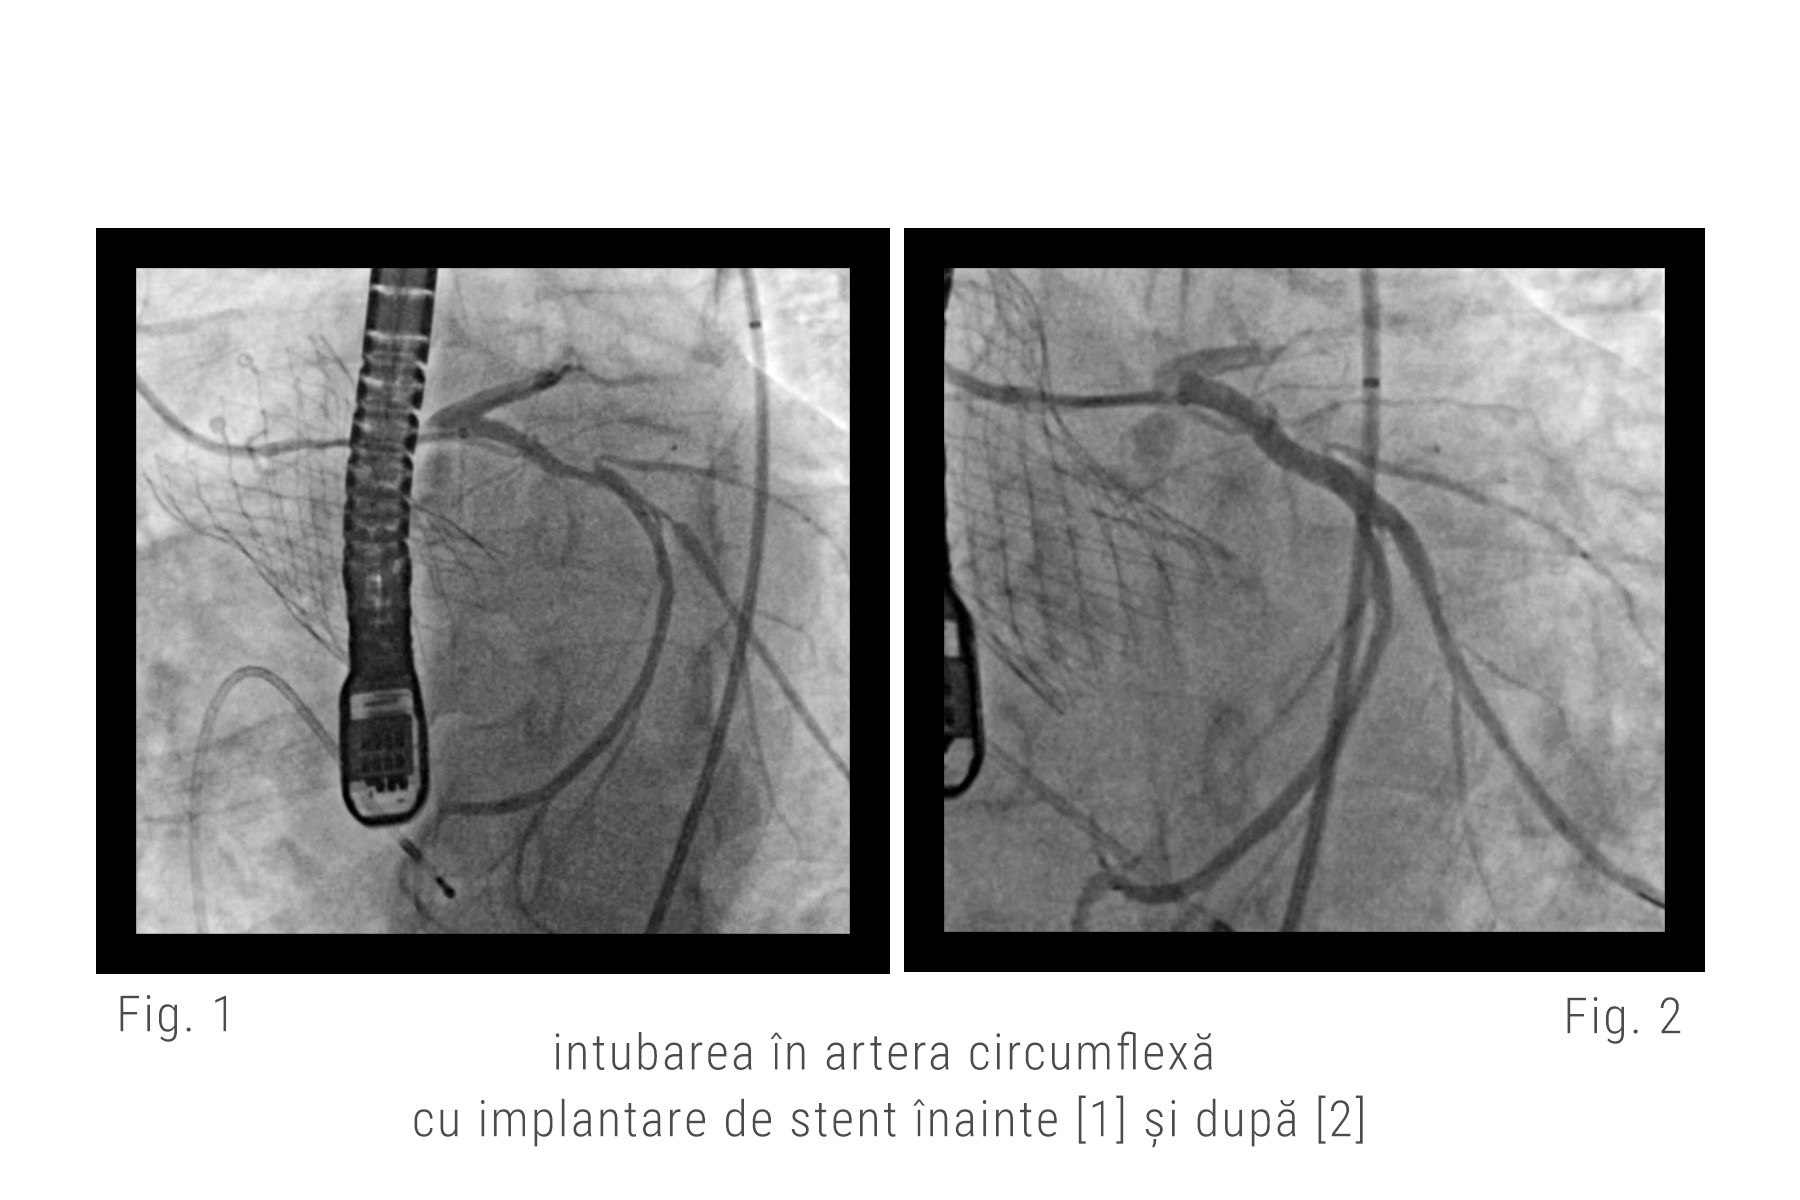

Echipa noastră de medici a decis să rezolve cazul prin implantarea mai întâi a unei valve autoexpandbile Evolute ProPlus (Medtronic), pentru a ușura sarcina inimii de a ejecta sângele (decizie care s-a dovedit corectă, pentru că după implantare s-a observat imediat o ameliorare a contractilității, cu o creștere a fracției de ejecție la 30%). A urmat apoi, în continuarea intervenției, revascularizarea arterelor coronare cu ajutorul unui artificiu tehnic prin care s-a folosit o extensie pentru cateterul standard cu care au putut fi canulate selectiv ambele ramuri ale arterei coronare stângi pentru a implanta cu succes stenturile.